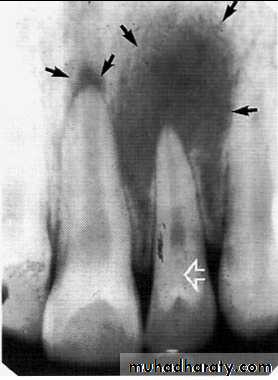

The radiograph shows erosion of the alveolar bone (o) and elevation

of the floor of the nasal fossa (arrows).• Globulomaxillary Cyst

• Located between the lateral incisor & cuspid teeth, the teeth are vital . Radiographically;an inverted• pear shape radiolucency

• between the roots of lateral & cuspid teeth, the roots of teeth pushed apart.